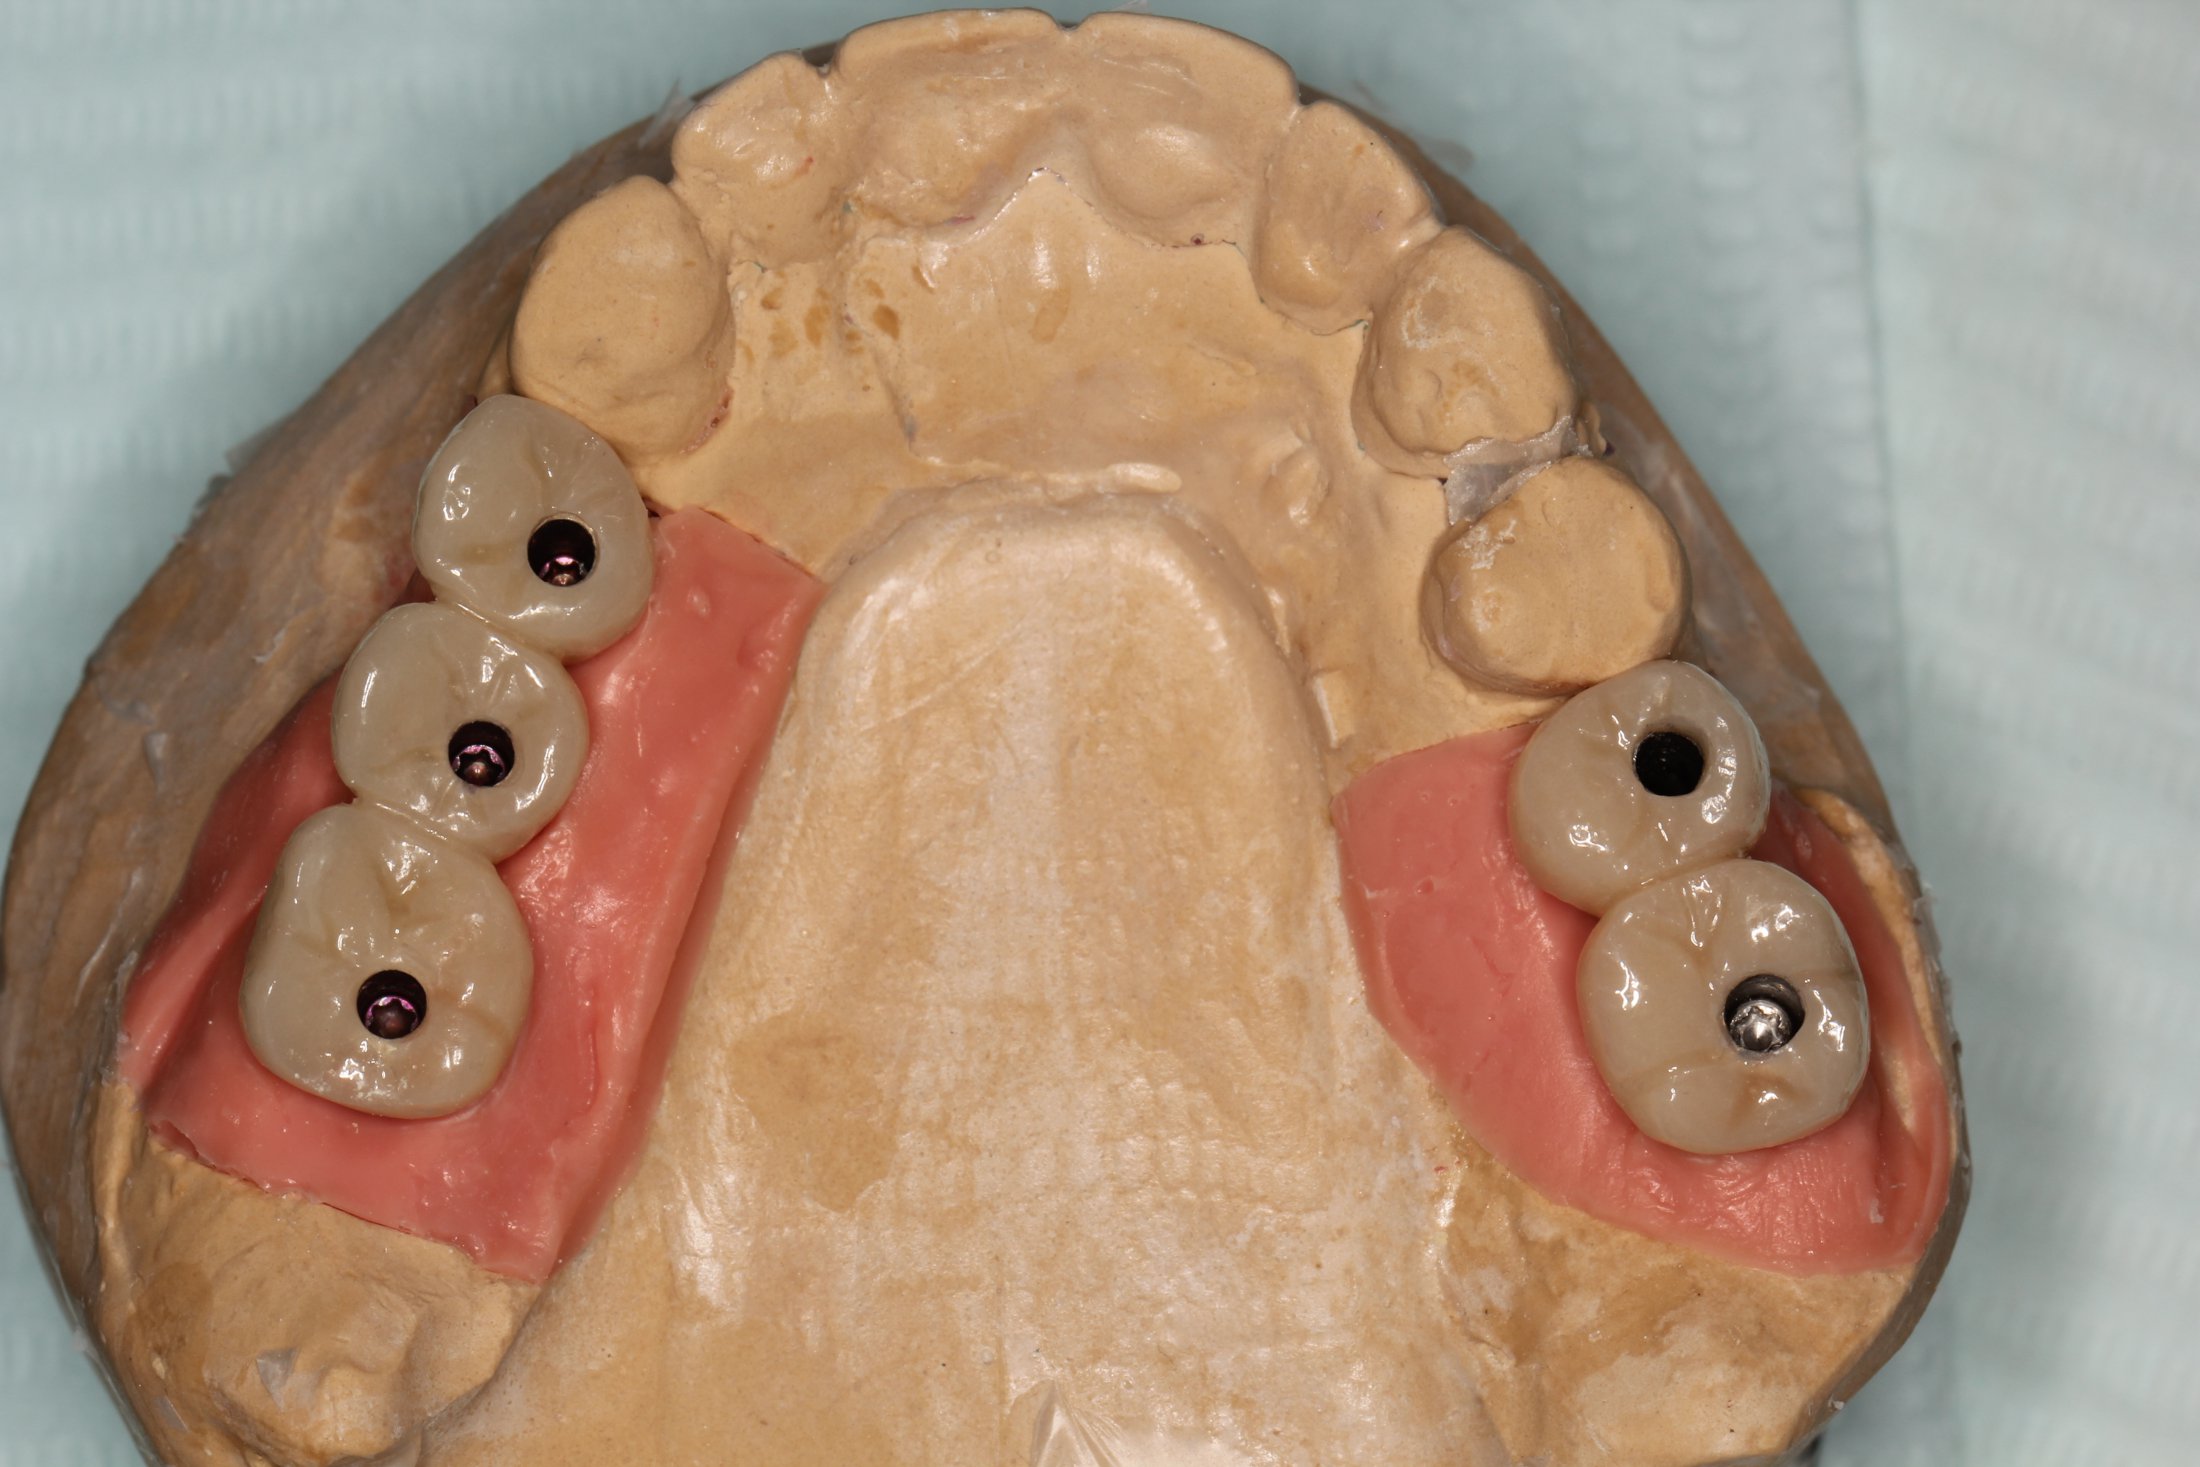

Sinus Lift Implant Vancouver Burnaby Periodontist Implant Dentist IMPreESS Perio

Dental Implant Centre in Vancouver Burnaby Sinus Lift Dental implant Surgery Dr. Noroozi Implant Specialist IMPrESS Perio Implant Center.001

Sinus Lift, Bone Graft, Implants Dr. Noroozi IMPrESS Perio Implant Center